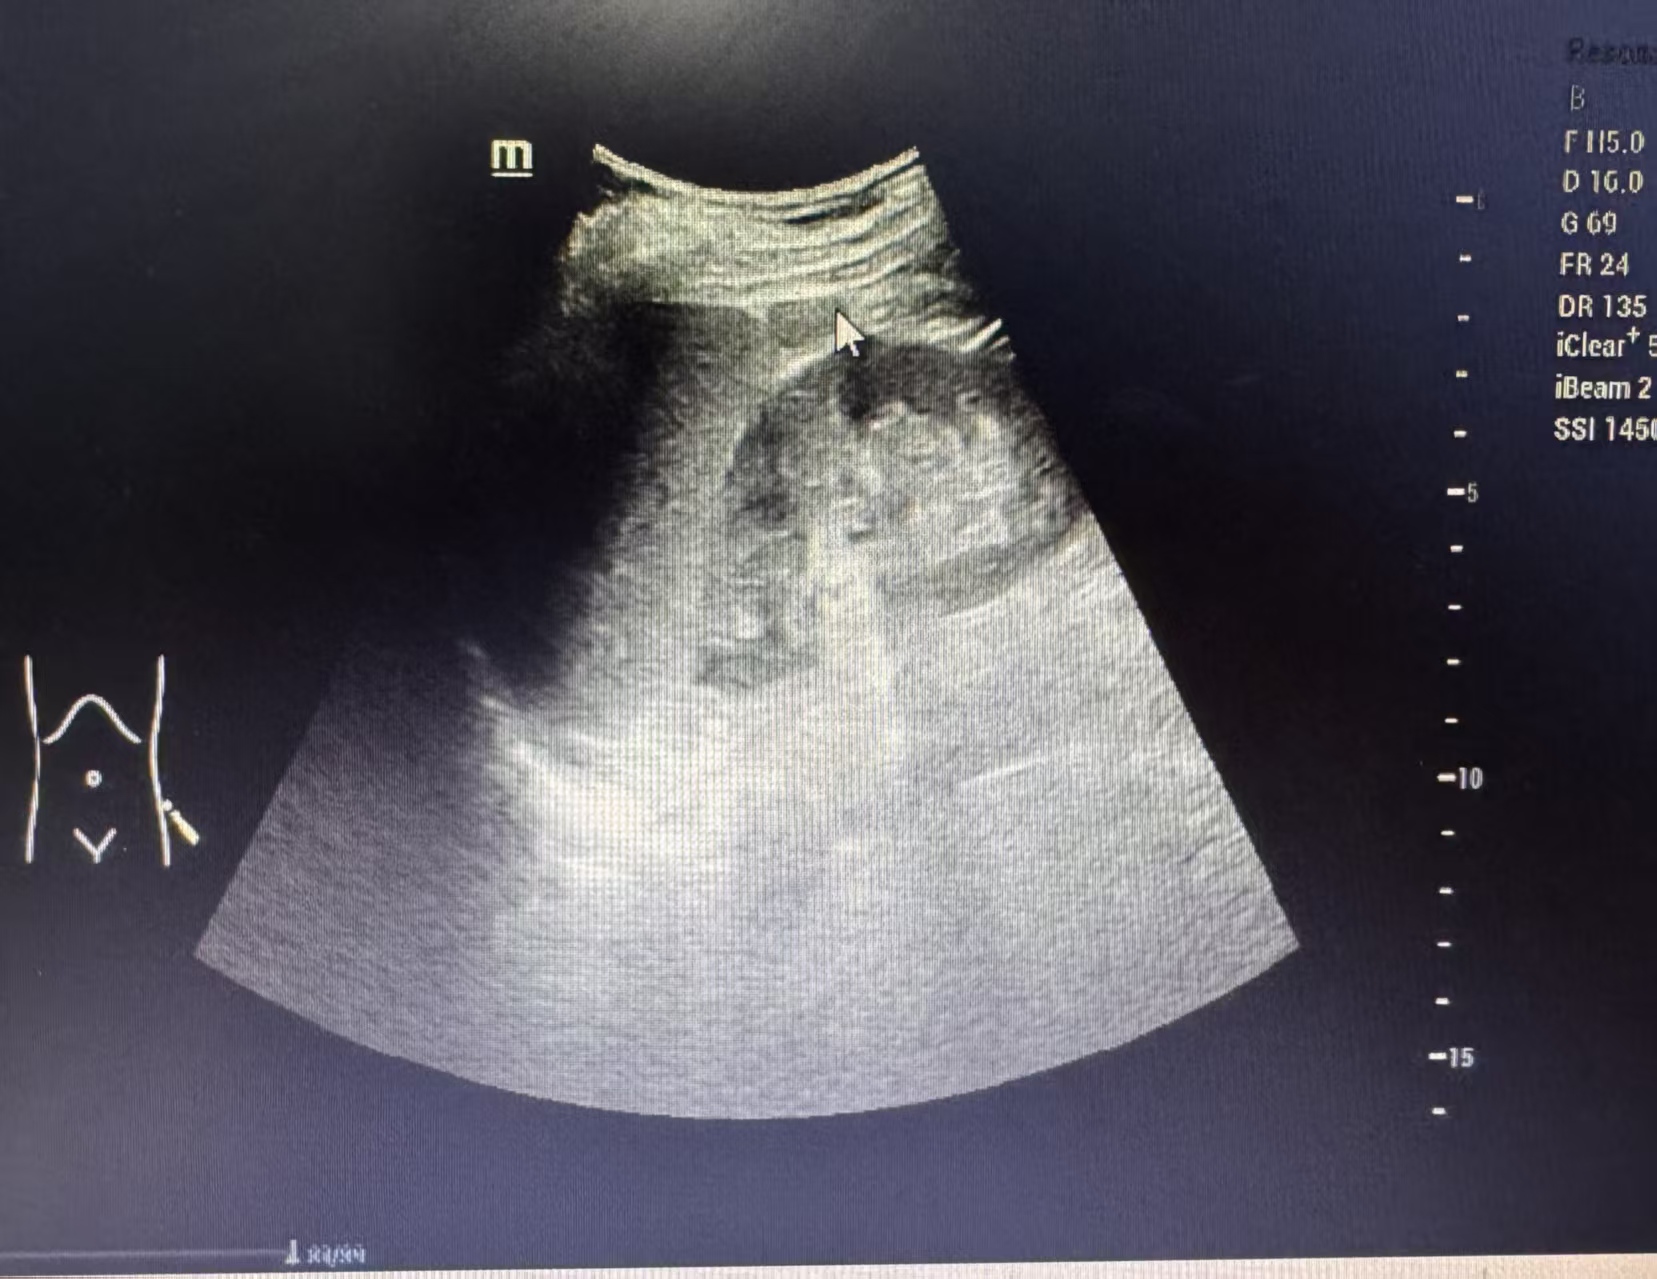

超声眼里的“小间谍”长啥样?

做超声检查时,副脾逃不过医生的“火眼金睛”。它通常有几个明显特征:

1. 位置固定

最爱躲在脾脏的“家门口”,也就是脾门附近,像个忠诚的小跟班。偶尔也会跑到胰尾附近。

2. 外形圆润

大多呈边界清晰的圆形或椭圆形,直径通常在1-2厘米,像个光滑的小球。

3. 善于伪装

这点最关键!在超声图像上,副脾的回声质地和主脾脏一模一样。这就是判断它是副脾而非其他肿物的核心依据。